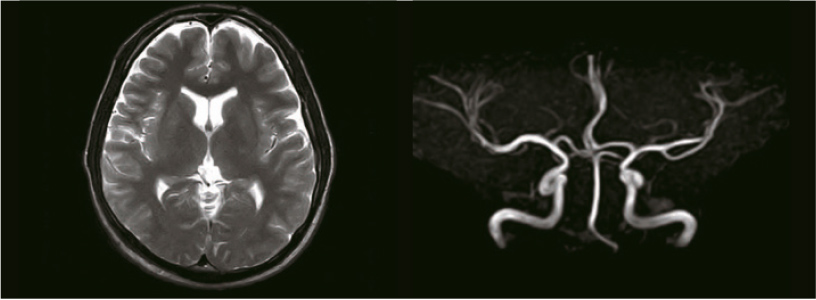

Our magnetic circuit technology and diagnostic functions enable crisp, high-definition imaging of clinically challenging regions and applications.

T2WI

T1WI

T2*WI